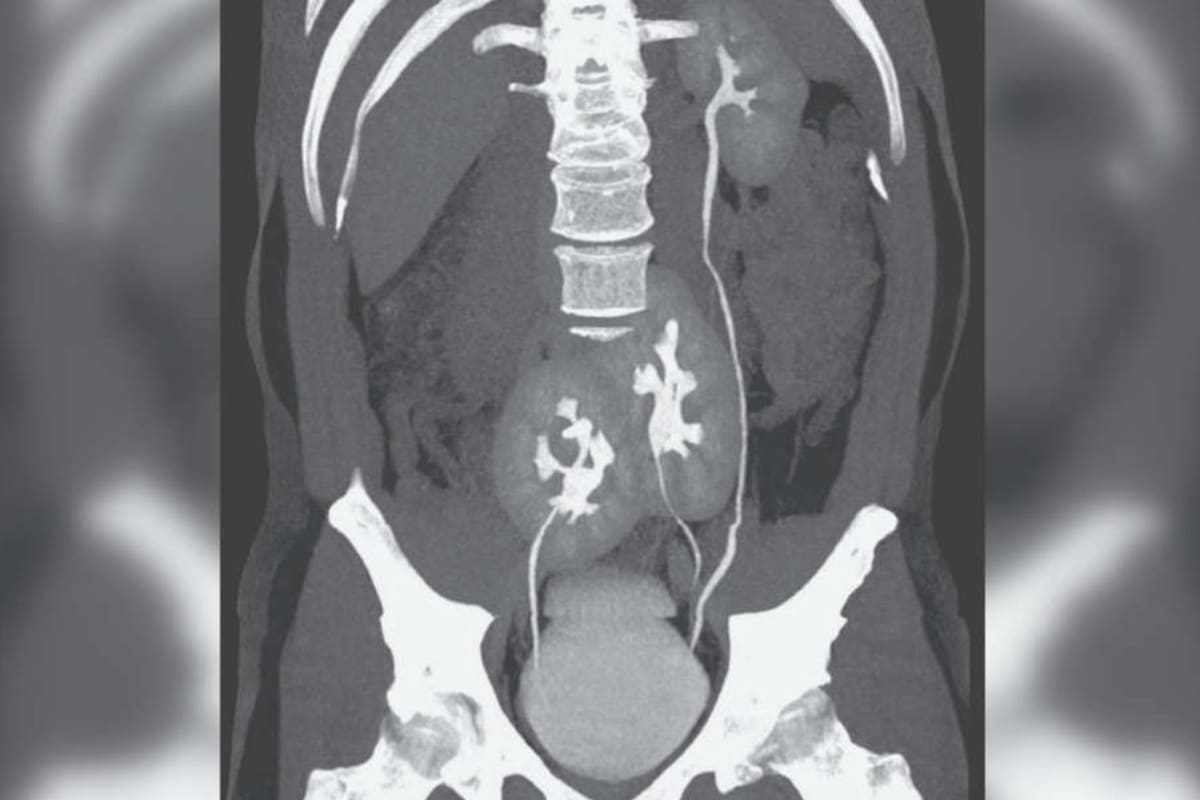

Ellos explicaron que, al llegar el paciente con su problema en la espalda, creyeron que podría tratarse de una hernia de disco, pero al realizar una tomografía computada descubrieron que el hombre tenía tres riñones, en lugar de dos. El riñón izquierdo tenía la apariencia normal, mientras que en el lado derecho tenía dos riñones fusionados.

Renato Foresto, uno de los médicos que realizaron el descubrimiento y el posterior informe para la revista científica, expresó la primera impresión al percibir en la imagen de la tomografía los tres órganos: "Nunca habíamos visto algo así. Fue una sorpresa, seguida de la preocupación de que hubiera algo mal con la salud del paciente".